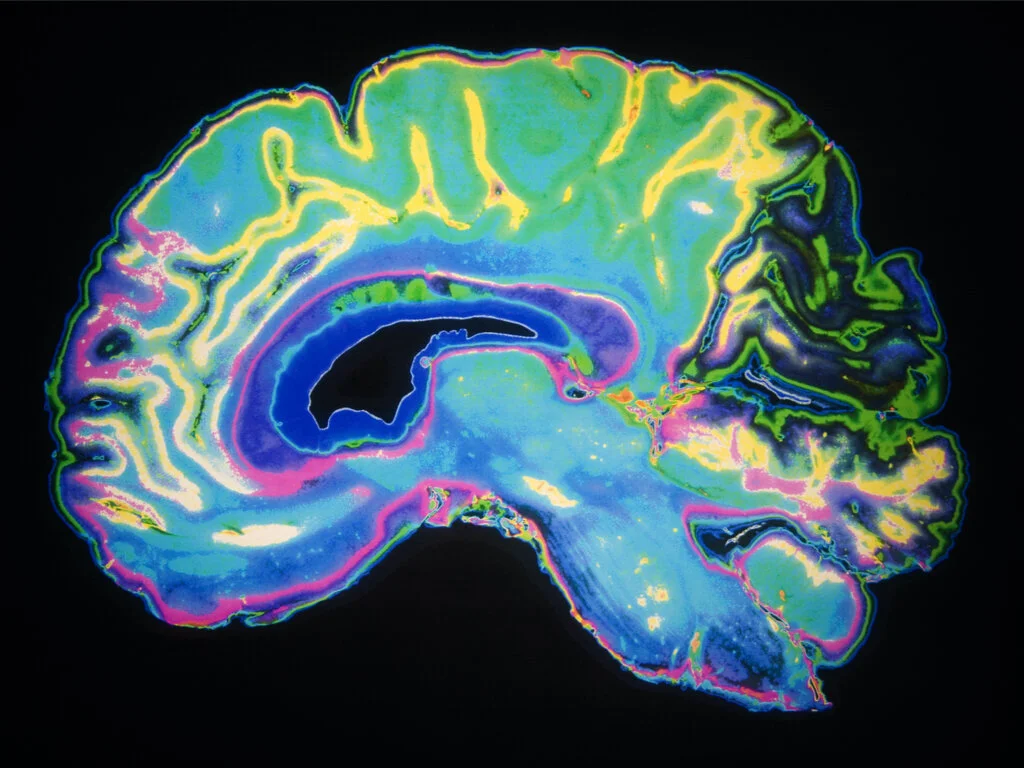

Sleep restores our bodies and brains by modulating brain activity to enable better thinking, learning, and memory. The traditional view holds that poor sleep is a symptom of poor brain health. Instead, it is becoming clear that there is a bidirectional relationship between sleep and brain health in which sleep problems may be both a cause and consequence of brain health problems.

The team at Sleep and Brain takes a holistic approach toward sleep. Rather than view sleep in isolation, we untangle the complex dynamics between sleep and your brain, breathing, physical development, and life experience. We utilize sophisticated brain mapping, precise muscle strength determinations, advanced sleep tests, objective nasal flow and resistance measurements, and unique facial analysis to identify the imbalances that fragment your sleep. We can then institute targeted treatments to restore sleep and balance to your life.